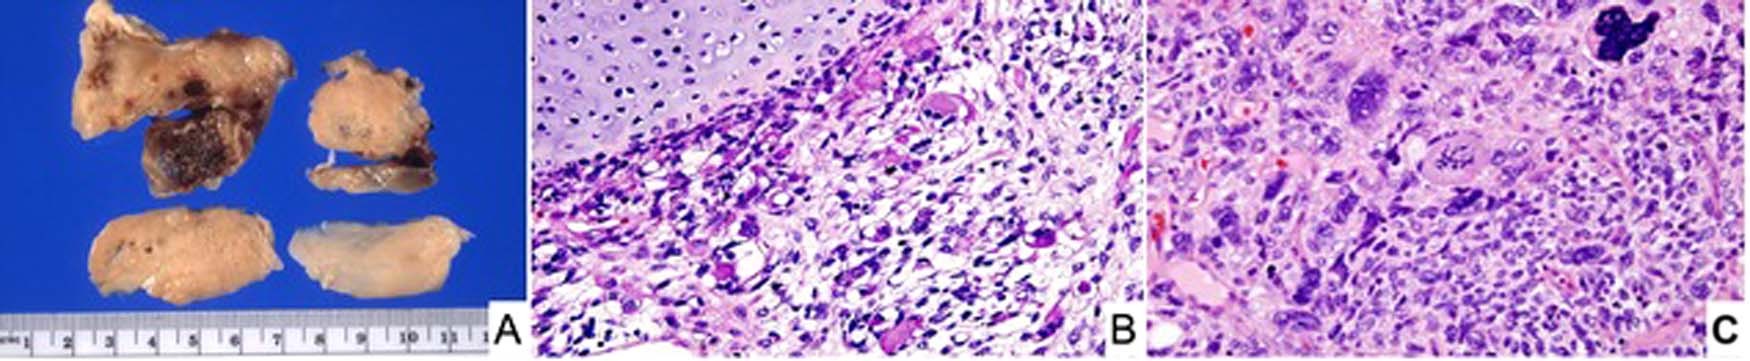

Fig. 1: Pleuropulmonary blastoma, type III.

A Pleuropulmonary blastoma, type III occurring in a 3-year-old male as a large solid thoracic mass. Piecemeal resection revealed a tan-white, myxoid and hemorrhagic neoplasm (one of the original 11 PPB cases). B Focus of embryonal type rhabdomyosarcoma and nodule of malignant cartilage. C Another focus of primitive sarcoma with individual anaplastic cells including bizarre mitotic figure.